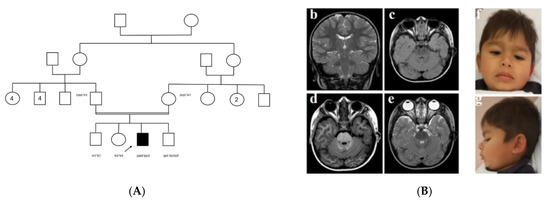

| Brain Abnormalities | Mild dilatation of periencephalic spaces | Arnold Chiari type I, ectopic neurohypophysis, mild cerebellar vermis hypoplasia | MTS, dysgenesis of the corpus callosum, ectopic posterior, and hypoplastic anterior pituitary | Mild MTS, bilateral polymicrogyria, hydrocephalus, diffuse white matter alterations, thin corpus callosum | MTS, agenesis of the corpus callosum, pituitary hypoplasia, hypothalamic hamartoma | MTS (both), thin corpus callosum (one) | MTS and hypoplastic pituitary in one, cerebellar vermis hypoplasia in two |

| Facial Features | Thick lips, cupped ears, anteverted nares, wide and sparse eyebrows | Frontal bossing, sparse and broad-arched eyebrows, hypertelorism | Sparse hair, hypertelorism, thick eyebrow, bilateral ptosis, short columella, low-set ears | NR | NR | NR | Ptosis, frontal bossing, hypertelorism, anteverted nares |

| Other birth defects | Esophageal atresia, post-axial polydactyly, heart defect | Cryptorchidism | Micropenis, cryptorchidism, hand and feet brachydactyly, cleft lip and palate | NR | NR | No | One with micropenis and cleft lip and palate |